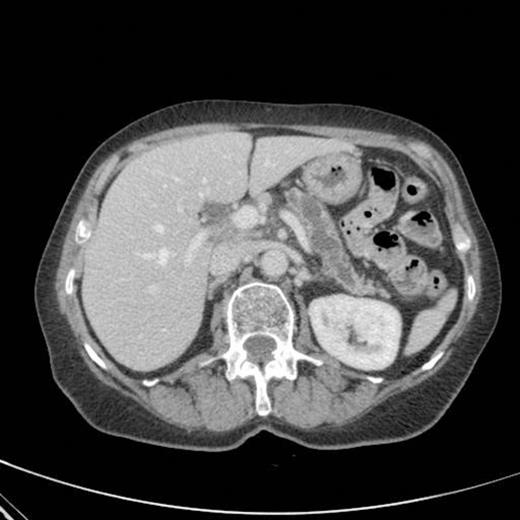

CT scan showing marked dilatation and tortuosity of the main pancreatic duct (12-13mm at the head) with atrophy of the body and tail

CT scan done 2 years later revealed marked dilatation and tortuosity of the main pancreatic duct (12-13mm at the head) with atrophy of the body and tail (Fig1). Repeat scans done on an yearly basis over the next three years reported no progressive change. CT scan done 6 years after the original diagnosis revealed pancreatic duct dilatation to 15 mm with side branch dilatation in uncinate process and atrophic pancreas (Fig 2). A diagnosis of mucinous ductal ectasia or an intraductal papillary mucinous tumour was suggested. On clinical review, patient complained of epigastric discomfort, loose stools, anorexia and weight loss. Upper GI endoscopy and colonoscopy was normal. Faecal elastase was less than 100 confirming pancreatic insufficiency for which she was commenced on creon.